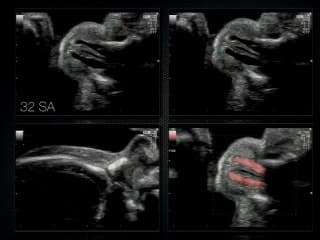

La médiathèque du Collège Français d'Échographie Fœtale (CFEF) constitue l'une des plus importantes collections de ressources vidéo dédiées à l'échographie fœtale en France. Avec plus de 3 261 vidéos, elle couvre l'ensemble des thématiques liées à la pratique échographique prénatale.

Vous y trouverez des conférences présentées lors des congrès nationaux et internationaux, des cours magistraux dispensés par des experts reconnus, des démonstrations pratiques sur des cas cliniques réels, ainsi que des podcasts et tables rondes sur les dernières avancées de la spécialité.